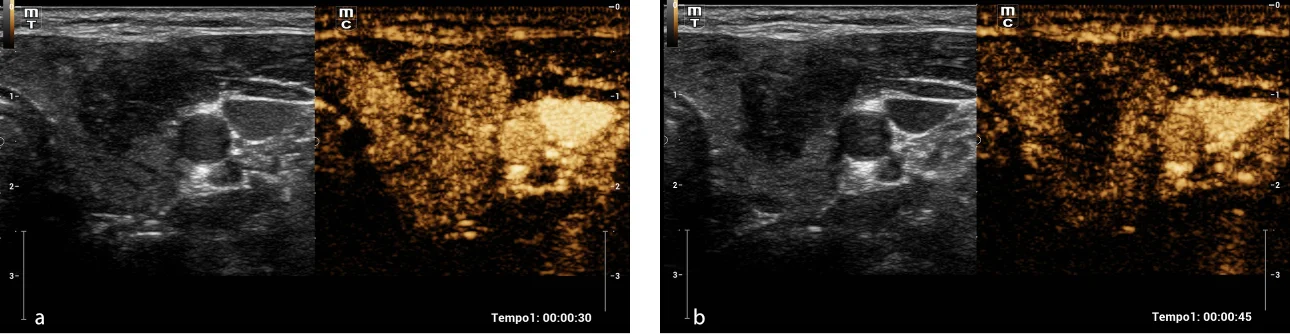

Fig. 3. Contrast ultrasound (CEUS). Heterogeneous iso-enhancement of the thyroid nodule (a) is observed with early wash-out with respect to the thyroid parenchyma adjacent at 45 s (b).

Fig. 3. Contrast-Enhanced Ultrasound (CEUS). Heterogeneous iso-enhancement of the thyroid nodule (a) is observed with early wash-out with respect to the thyroid parenchyma adjacent at 45 s (b).

During the diagnostic process, thyroid ultrasound was performed using the Mindray Resona I9 system. A solid, hypoechoic nodule was observed on the left side which was wider than high and had apparent extrathyroid extension and punctate echogenic foci. Additionally, internal vascularity was observed upon application of color Doppler. This nodule was evaluated as ACR TI-RADS 5 based on the findings (Fig. 1). Similarly, the Smart Thyroid AI of Resona i9 ultrasound system program was used to measure and analysy malignant signs and yielded comparable findings, except for the extrathyroidal extension which was assessed as having lobed/irregular borders. However, it also garnered an ACR TI-RADS 5 score (Fig. 2). The elastography examination indicated a heterogeneous appearance with an Emax stiffness of 40.53 kPa . Finally, the CEUS revealed that the lesion was heterogeneously iso-enhanced in comparison with thyroid parenchyma that showed early washout at 45 seconds (Fig. 3). The central portion of the nodule achieved peak intensity of 26.7 dB at 26.8 seconds, correspondingly; while the peripheral portion achieved peak intensity of 29.1 dB at 22.3 seconds (Fig. 4 ). The patient underwent Fine Needle Aspiration (FNA), which yielded a histopathological report of category VI of the Bethesda system, indicating papillary thyroid carcinoma. Additionally, confirmation of invasion in the prethyroid muscles was obtained during the surgical procedure.

In recent years there has been an increase in the prevalence of thyroid nodules. High-resolution ultrasound is the most important imaging modality for the evaluation of a thyroid nodule. [3] However, initial ultrasound alone is not always effective in achieving characterization. That is why, especially in recent years, it has become increasingly necessary to develop other imaging modalities to limit the use of FNA or even diagnostic thyroidectomy as much as possible. [2] Contrast-Enhanced Ultrasound (CEUS) is considered an effective technique for assessing the microvasculature, estimating the sequence and intensity of vascular perfusion, as well as hemodynamics in the thyroid nodule, providing real-time characterization of the nodule, and is considered a valuable new approach in the differentiation of benign versus malignant nodules. [1, 3] Several studies have shown that there are certain characteristics of CEUS that suggest malignancy, including late filling, heterogeneous enhancement, poorly defined enhancement edges, and rapid wash rate. [3] However, no statistically significant differences in absolute values of time to peak and peak intensity have been observed between malignant and benign nodules. [5] In our case, the nodule presented a heterogeneous enhancement with early wash-out, being highly suggestive characteristics of malignancy. Most malignant nodules contain areas of fibrosis, calcification, or focal necrosis, which may explain the tendency to heterogeneous enhancement. Some published studies have shown that early washout could be due to shrinkage of microvasculature in carcinomas as a result of necrosis. [1] Regarding elastography, there is no established parameter on the behavior of malignant thyroid nodules. In some studies, there has been a trend towards increased stiffness, although the findings have not yielded a specific quantitative value. [1] In our case, we observed similar behavior, with a heterogeneous appearance and areas of increased stiffness.